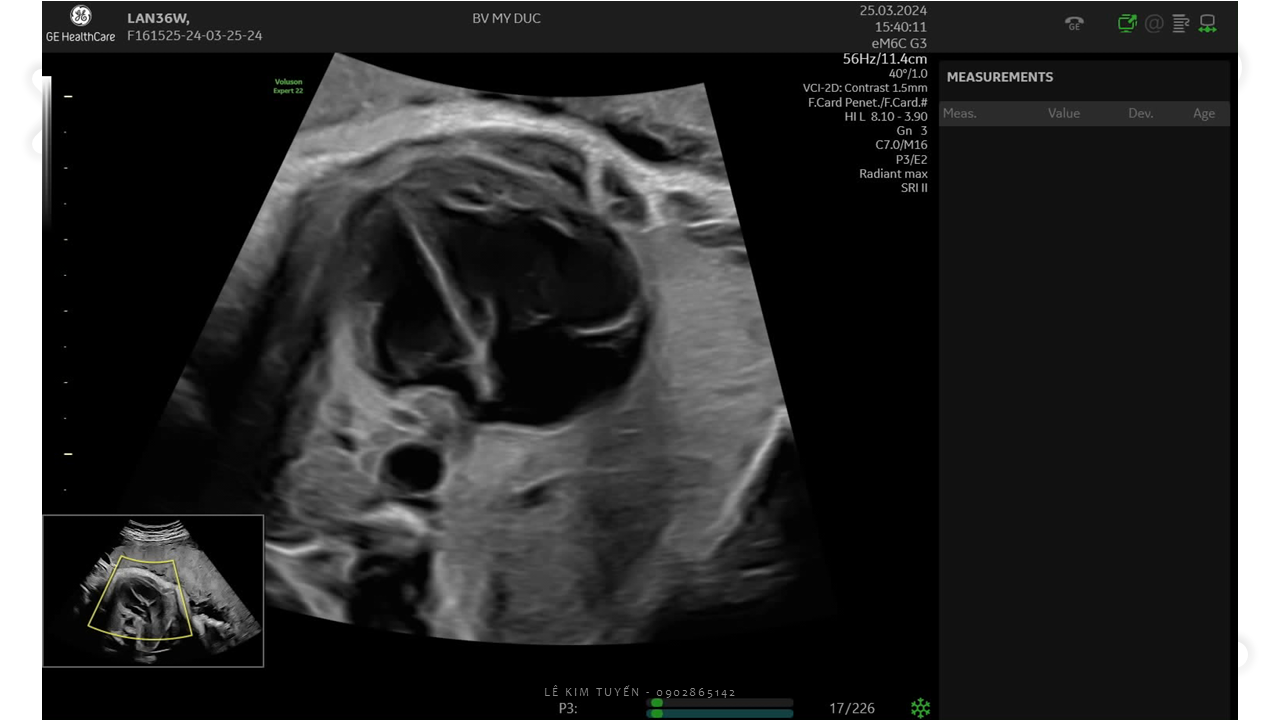

Siêu âm tim thai - Các kỹ thuật hiện đại

TS. BS. Lê Kim Tuyến

Bệnh viện Tim Tâm Đức